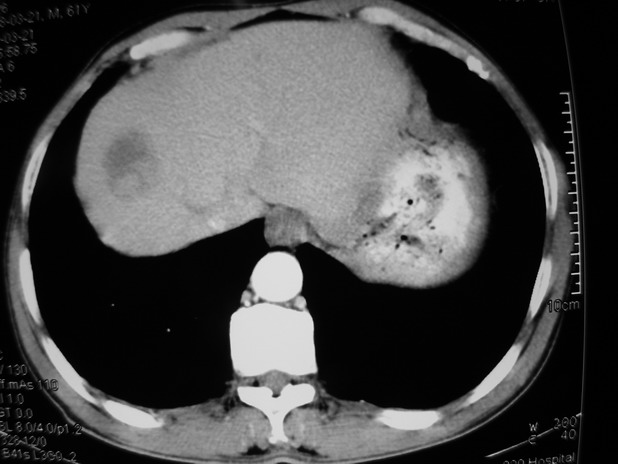

以下是引用余辉在2009-3-21 21:36:00的发言:[br]图像太乱了,建议楼主直接将强化数据按顺序列出来,病灶位置较表浅薄,有肝炎病史,灶内实性成分有显著强化,动脉期约60hu,考虑肝癌可能性大,进一步检查。